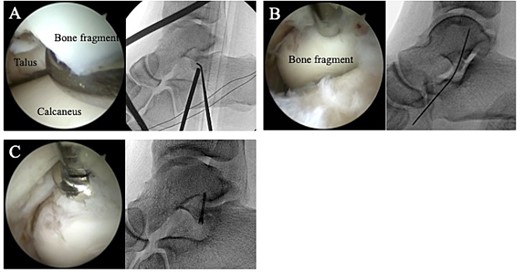

A 24-year-old male basketball player presented to our hospital complaining of left lateral ankle pain during a cutting motion. His height, weight, and body mass index were 172 cm, 64.0 kg, and 21.6 kg/m2, respectively, and he had no history of previous medical conditions. On his first visit to our hospital, he could not walk due to pain. Physical examination revealed swelling, ecchymosis, and tenderness at the lateral aspect of his left ankle. The American Orthopedic Foot and Ankle Society (AOFAS) score was 32 out of 100 points. Plain radiographs of the left ankle showed no abnormal findings in the anteroposterior view, but a fracture line was discovered at the base of the lateral process of the talus in the lateral view (Fig. 1). Non-contrast computed tomography (CT) showed a simple fracture line that extending from the talofibular articular surface down to the posterior talocalcaneal articular surface of the subtalar joint. In addition, the bone fragment was displaced >2 mm (Fig. 2). The patient was diagnosed with Type I LPFT and underwent surgical treatment.

Plain radiographs of the left ankle showed no abnormal findings in the anteroposterior (A) view, but a fracture line was discovered at the base of the lateral process of the talus in the lateral (B) view.

The surgery was performed under general anesthesia in the lateral position, with the affected side up. A thigh air tourniquet and a fluoroscopy were used. First, 3 ml of normal saline was injected into the sinus tarsi. A viewing portal was then made above the sinus tarsi, and a working portal was made 2 cm anterior to the viewing portal. A 30° arthroscope with a diameter of 2.7 mm was used to observe the fracture site (Fig. 3A). The synovium, adipose tissue and coagulation clot surrounding the fracture site were removed with a 3.0-mm-diameter motorized shaver, and the bone fragment was reduced using a guidewire sleeve and fixed with a 0.8-mm guidewire (Fig. 3B), the fragment was fixed through the guidewire with a cannulated double-threaded screw (Double Thread Screw Japan Mini, Meira, Nagoya, Japan) (Fig. 3C). After confirming that the bone fragment was fixed in the correct position under a fluoroscopy, the wound was sutured, and so the surgery was concluded (Fig. 4).

(A) A 30° arthroscope with a diameter of 2.7 mm was used to observe the fracture site. (B) The bone fragment was reduced using a guidewire sleeve and fixed with a 0.8-mm guidewire. (C) The fragment was fixed through the guidewire with a cannulated double-threaded screw.